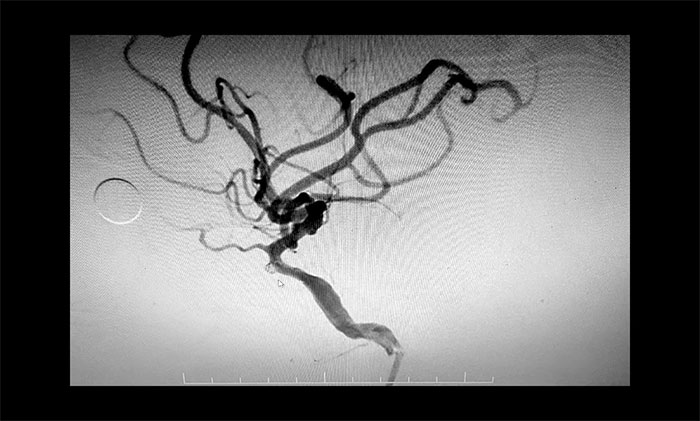

在明确告知患者家属手术风险,并取得同意后,于耀宇主任团队在麻醉科和介入手术室紧密配合下,为患者开展经导管颅内动脉瘤弹簧圈栓塞术。手术过程顺利,术后患者恢复情况良好。

▲ 动脉瘤顺利栓塞,不显影